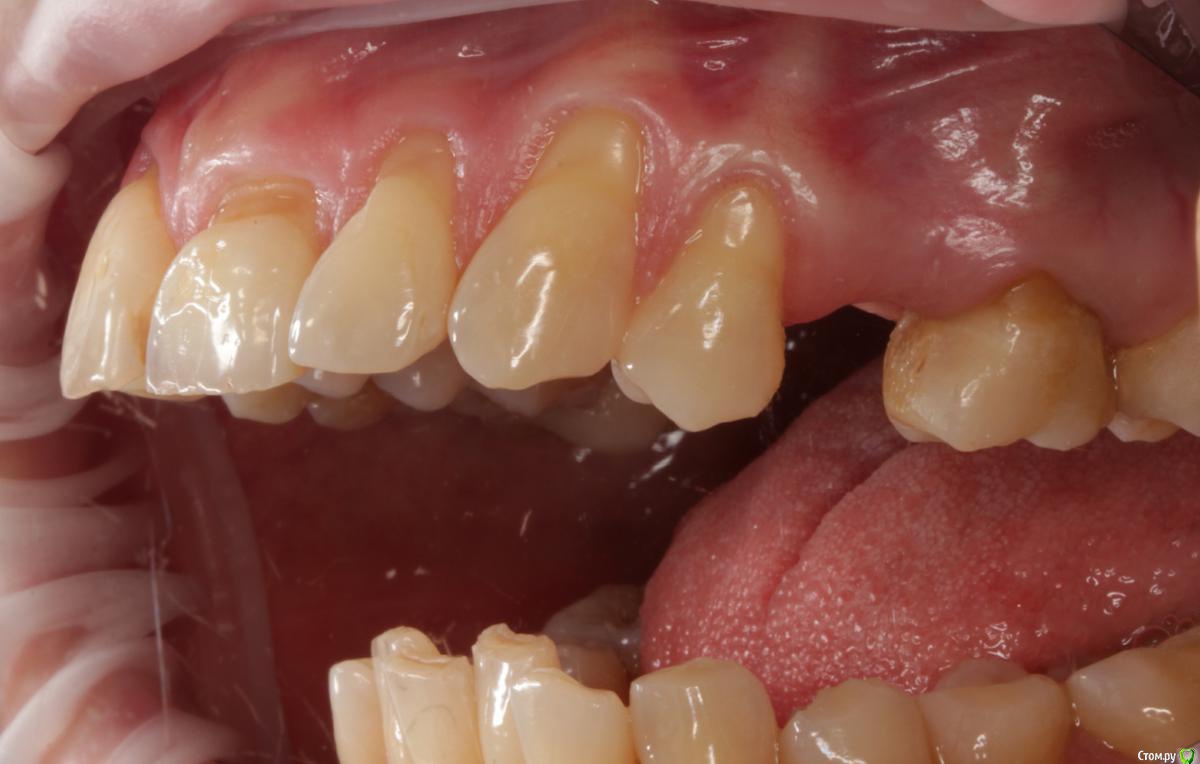

Dmitry DK Опубликовано 31 августа, 2019 Поделиться Опубликовано 31 августа, 2019 Доброго дня! Первичное обращение пациентки было связано с отсутствием 25 зуба, эстетические нарушения слизистой, клиновидные деф-ты в области других зубов - не смущали.В итоге решили, раз проводим операцию ( импл + ССТ ), закроем попутно и рец на верхней челюсти.Реставрацию на 21 зуб все не ставит... Приятных тебе выходных! ) Пациентка проходила лечение 2,5 года назад, пришла на проф осмотр 7 Ссылка на комментарий

Dmitry DK Опубликовано 4 сентября, 2019 Автор Поделиться Опубликовано 4 сентября, 2019 короткий зуб, что же еще.У имплантата край дёсны действительно корональнее.Платплатформа в двух миллиметрах от цементо-эмалевой границы, была возможность иссечь излишек либо его ещё отдавить, также как хотелось заполировать в 1-м сегменте, поставит реставрацию на 21-м и т.д.Пациентка отказалась от дальнейших этапов... Ссылка на комментарий